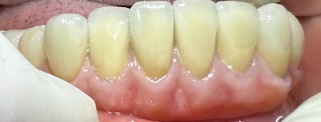

tiếp nối 1 số ca lẻ P1 Bạn D.H.L nữ 36 tuổi đến niềng hàm dưới để đóng kín khe thưa, bạn này thiếu 1 răng cửa dưới và kết quả sau 3 tháng hàm dưới đã đều và kín khe thưa. Bạn N.N.P.L nữ 12 tuổi đến niềng vì muốn làm […]